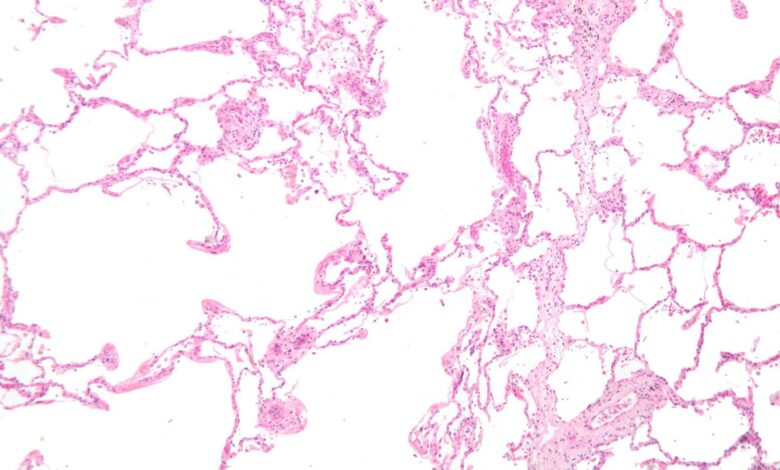

Micrografia mostrando enfisema (esquerda – grandes espaços vazios) e tecido pulmonar com relativa preservação dos alvéolos (direita). Crédito: Wikipedia, CC-BY-SA 3.0